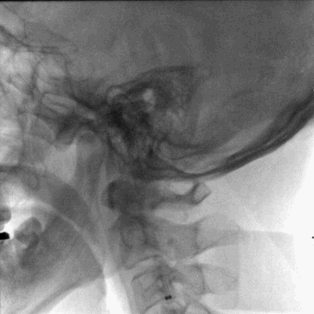

术前CT,ASPECT 8分。

术前CTA检查。

术前造影,BA近端闭塞。

术前造影,LC7次全闭塞。

术前造影,RICA 通过交通动脉向左侧颈内动脉及基底动脉尖代偿供血。